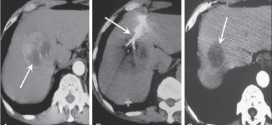

El hepatoma. Tumor maligno en general y especialmente el formado por células epiteliales, a saber. El hígado está situado en la parte superior derecha de la cavidad abdominal, debajo del diafragma y por encima del estómago, el riñón derecho y los intestinos. El hígado tiene forma cónica, es de color marrón rojizo oscuro y pesa alrededor de 3 libras. El …